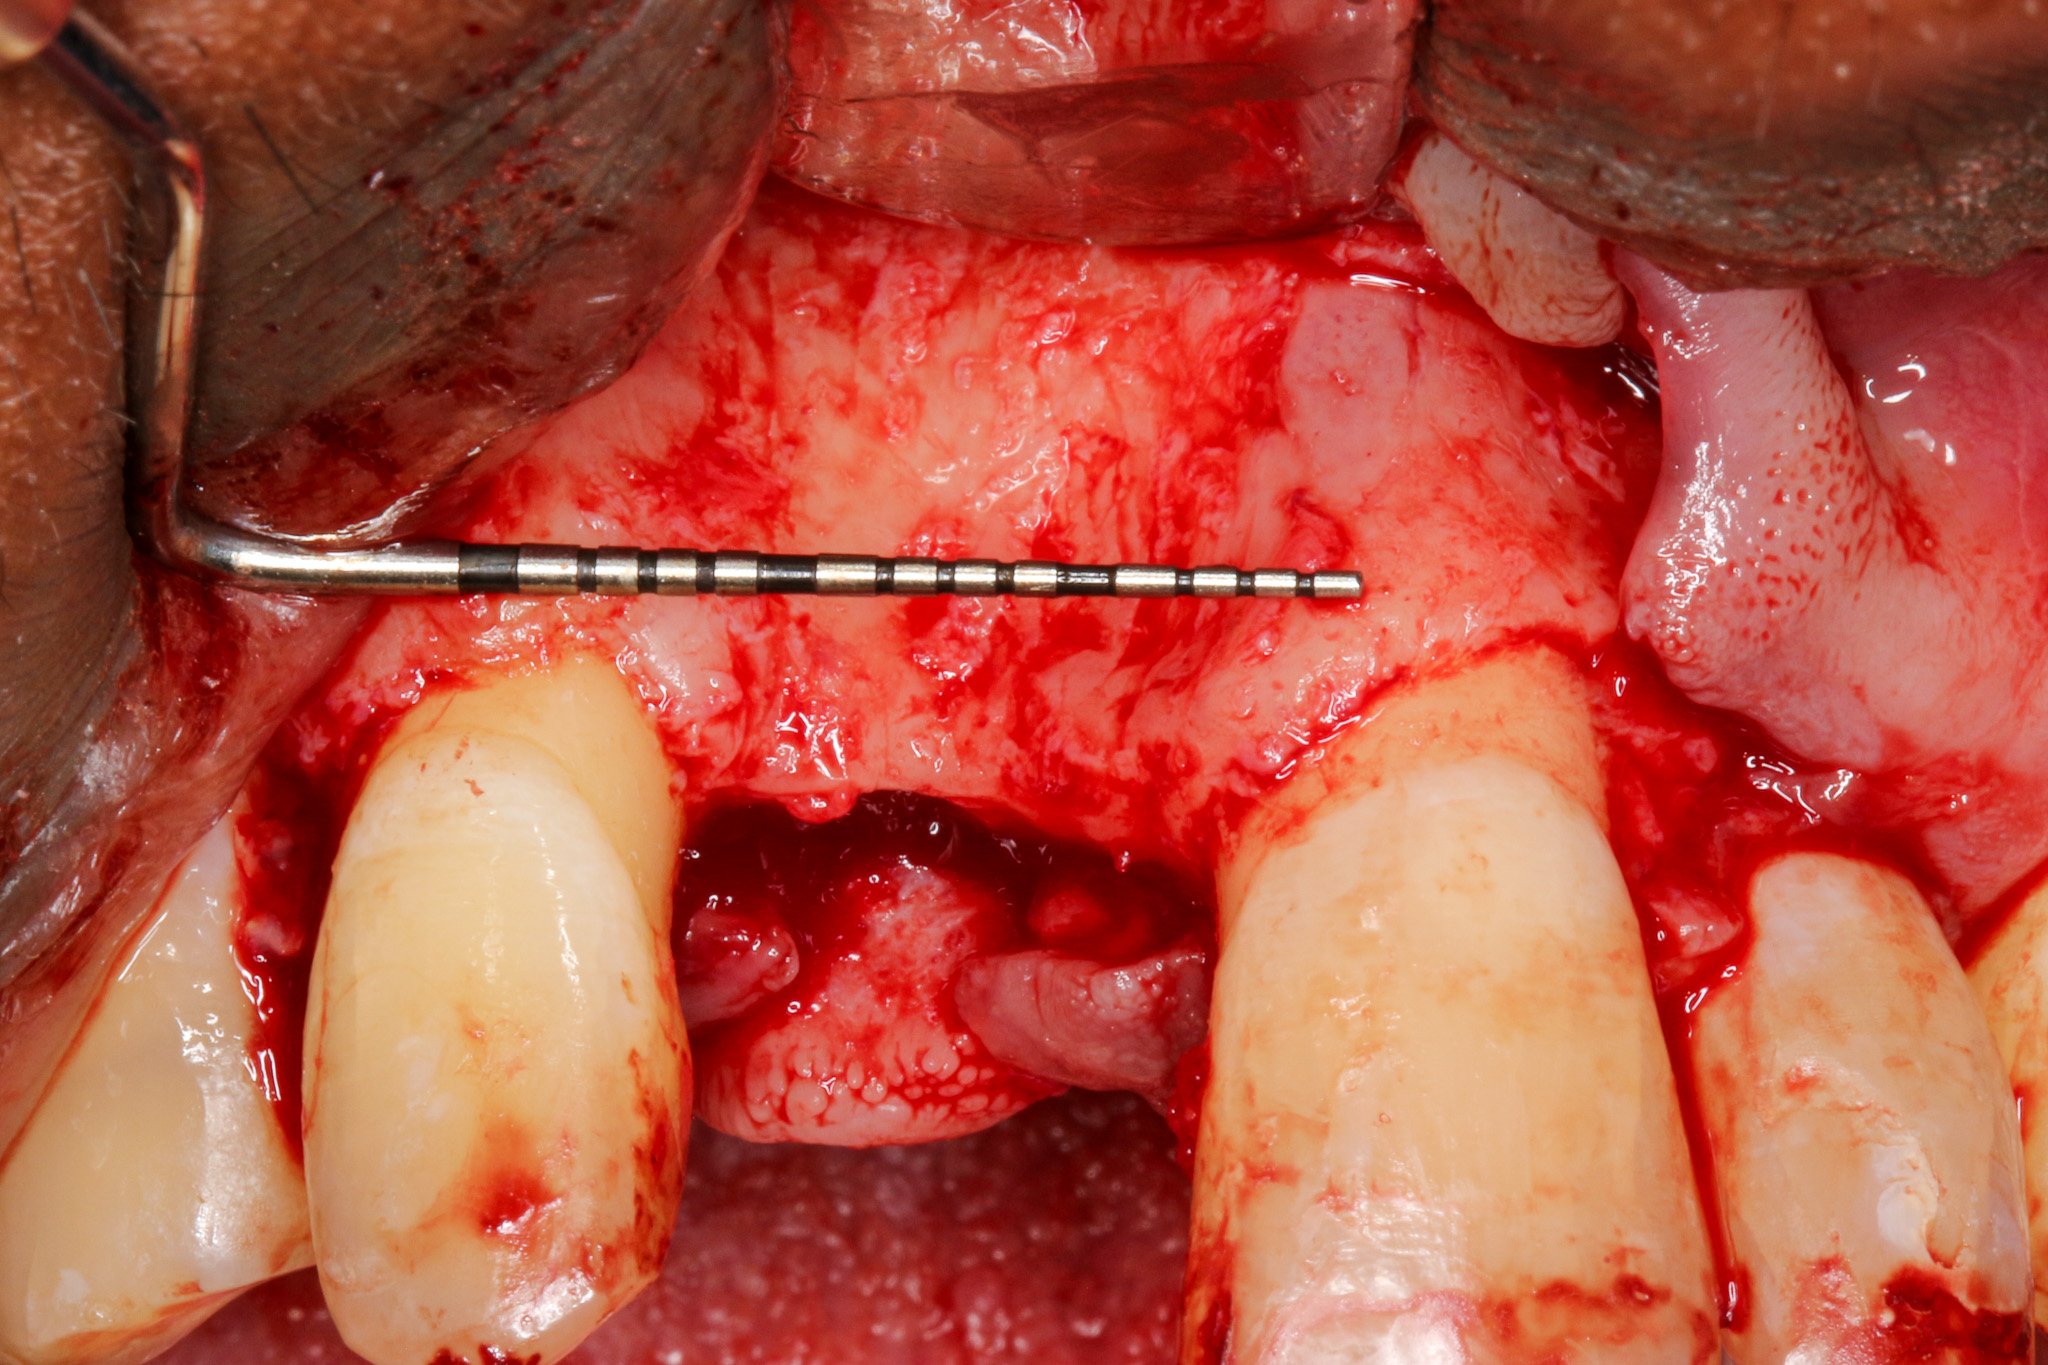

4 to 5 mm buccal bone dehiscence with concave morphology.

Thorough scaling and root planing of adjacent teeth was performed to minimize bacterial load as periodontal health is critical for GBR success; inflammatory conditions can compromise graft integration and membrane barrier function (Simion et al., 1994)